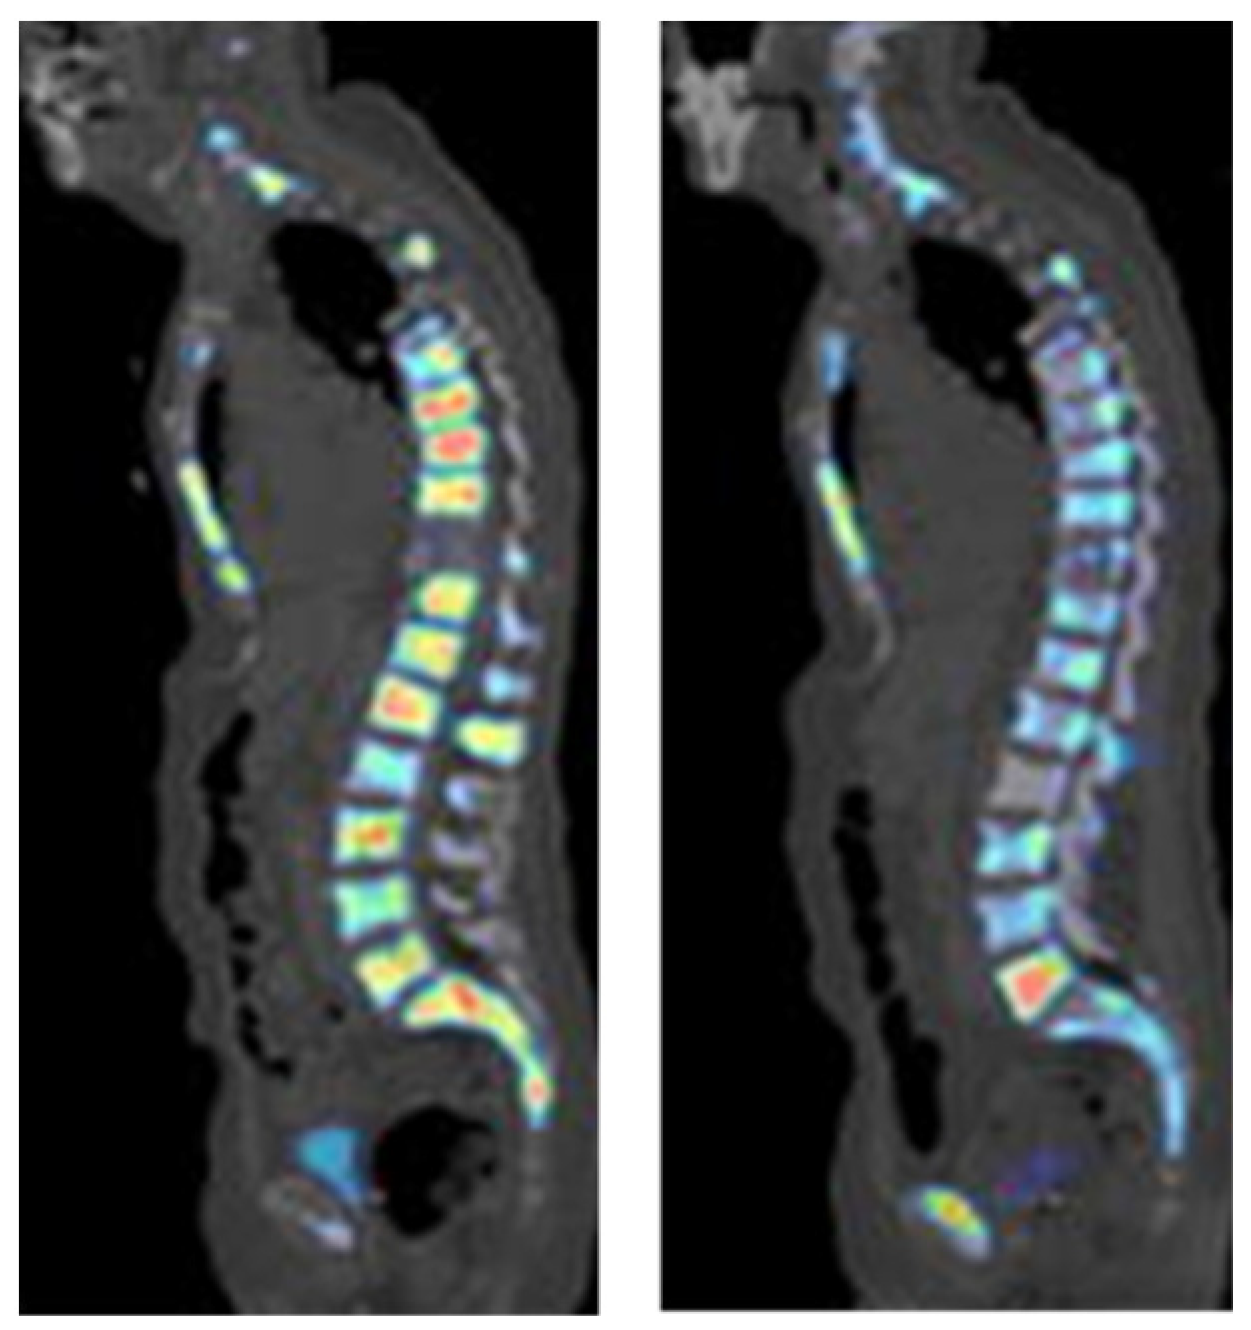

[18F]-NaF was first applied in diagnosing osteogenic activity four decades ago. The mechanism of action for [18F]-NaF in the detection of bone lesions, including metastases, is based on the chemisorption of [18F]F into hydroxyapatite, a bone component. Because of limited development of PET cameras at the time, this agent was not widely used and, therefore, other technologies, such as bone scintigraphy and SPECT were employed [98]. However, the specificity of SPECT was low and its acquisition times were long. In the last ten years, with the development of PET scanner technology, [18F]-NaF, was approved by the FDA for the indication of altered osteogenesis. It has been extensively applied for bone lesion detection in PCa (Figure 7). The performance of this imaging agent has been investigated in the following scenarios: for the detection of bone metastases in PCa patients, for the monitoring of treatment response, and for other aspects of utility, such as in combination with other imaging agents, for the detection of PCa.

Figure 7. [18F]Fluoride PET imaging of a PCa patient before (left image) and after (right image) treatment with dasatinib. This research was originally published in the Journal of Nuclear Medicine (JNM) [99].

The pooled sensitivity and specificity for [18F]-NaF was 98% and 90%, respectively, which were higher than the sensitivity and specificity for both 99mTc-bone scintigraphy and 99mTc-SPECT or SPECT/CT [103]. When [18F]-NaF was compared with 68Ga[Ga]-PSMA-11 PET/CT in the detection of osseous metastases, the detection rate was about 30% higher for [18F]-NaF [104]. However, another study demonstrated that in PCa patients who had inconclusive results from [18F]-NaF PET/CT scans, an additional [68Ga]Ga-PSMA-11 PET/CT scan was able to precisely diagnose and change the patients’ management with an accuracy of 96% [105]. It has also been shown that [18F]-NaF can be useful in monitoring the treatment–response to chemotherapy with dasatinib in castration-resistant prostate cancer (CRPC). In that study, baseline scans were compared, with a scan taken 12 weeks after treatment, and the SUVmax had significantly decreased in metastatic bone lesions but not in normal bones [99]. Recently, it was also demonstrated that the combined use of [18F]-NaF and [18F]FACBC could detect soft tissue metastases and bone lesions simultaneously. The sensitivity and specificity of the combination increased, compared with either imaging agent used separately [106].